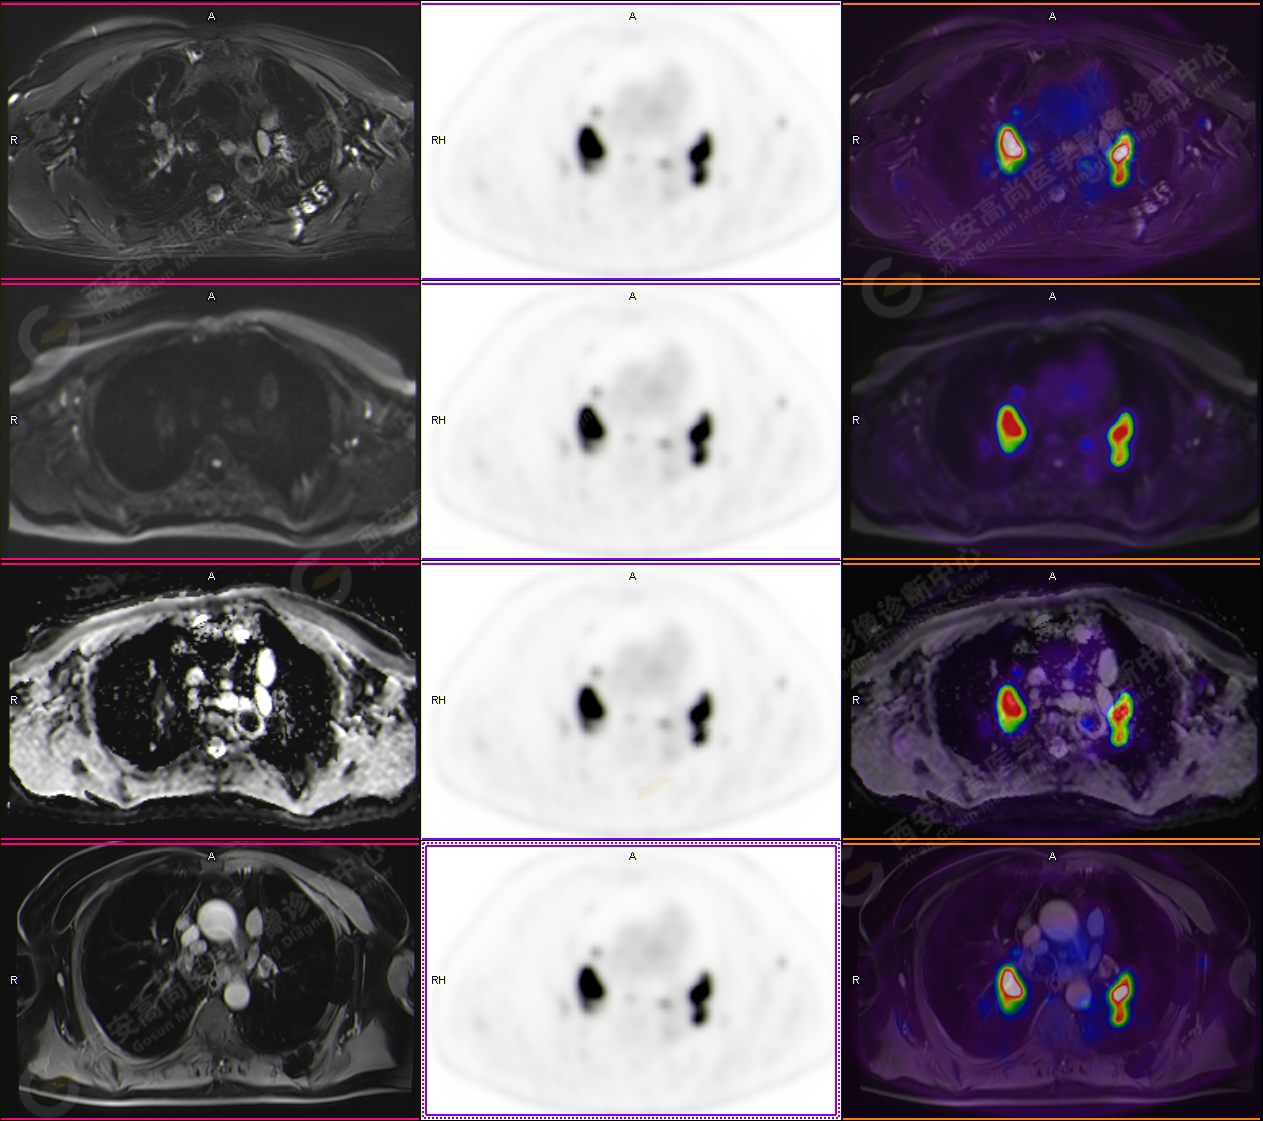

男性,53歲,頭暈半月入院,CT發(fā)現(xiàn)肺內(nèi)腫塊,雙肺多發(fā)大小不等實(shí)性及粟粒樣結(jié)節(jié),雙肺門(mén)及縱隔多發(fā)腫大淋巴結(jié)。病程中無(wú)發(fā)熱、胸悶氣及胸部不適。既往:左側(cè)肋骨外傷史。

PET-MR圖像